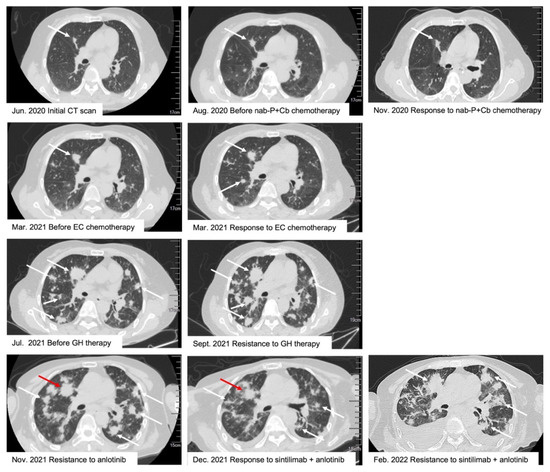

2. Case Presentation